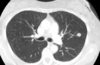

Consolidación alveolar

How well did you know this?